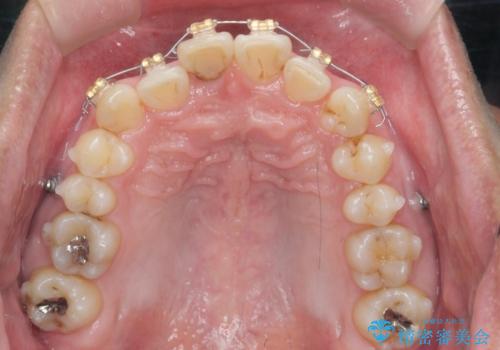

2級ディープバイト 遠心移動を伴うマウスピース矯正

・深い噛み合わせ(ディープバイト) ・2級性の咬合関係(上顎前突)・前歯のがたつき

以上のような歯並びの問題をマウスピース矯正インビザライン・カリエール・マイクロインプラント・部分ワイヤー矯正

を用いて改善していきます。

深い噛み合わせと上顎前突の状態を治すのに時間がかかりましたが、治療後は理想的で安定した咬合関係となりました。